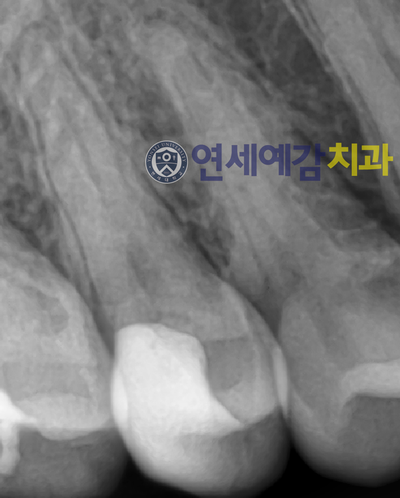

결과적으로 지금 5년여가 지난 저 치아의 상황은 어떨까요?

일단 지금까진 무리없이 잘 쓰고있습니다.